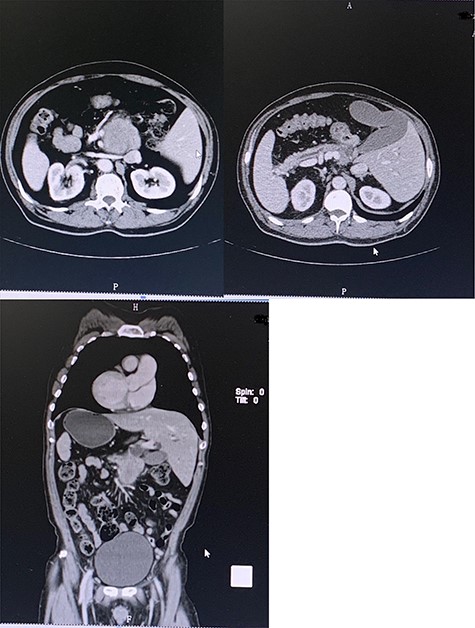

A 52-year-old male had no obvious inducement of epigastric pain for >3 months presenting persistent stabbing pain, accompanied by back pressure, fatigue, loss of appetite and hiccup. He went to a local hospital for treatment because of aggravated abdominal pain. Gastroscopy showed: (i) gastric polyps and (ii) chronic atrophic gastritis. The symptoms were not relieved after oral medication. Two weeks later he had jaundice with clay-like stool, so he went to the local hospital and underwent a color Doppler ultrasound examination. The results showed that: (i) visceral inversion; (ii) solid space-occupying at the head of the pancreas; (iii) dilated inner diameter of the intrahepatic and extrahepatic bile ducts and main pancreatic duct; (iv) fatty liver and (v) enlarged gallbladder volume and wall rough. The patient was admitted to our hospital complaining of ‘epigastric pain >3 months ago, jaundice with clay-like stool for 1 week’. The patient had no significant medical, surgical or drug history. Physical examinations were unremarkable except for a weight loss of ~20 kg since the onset of the disease. Blood and laboratory tests were carried out, and they showed elevated values of liver enzymes, with a clear elevation in the values of Enzyme gamma-glutamyl transferase (GGT) and alkaline phosphatase (ALP), as well as tumor markers CA19-9, CEA and CA72-4, which are indicative of the presence of an obstructive lesion (Table 1). After preoperative examinations, he was diagnosed with pancreatic cancer. His CT scan (Fig. 1) showed: (i) mirror dextrocardia; total visceral inversion; (ii) pancreatic space-occupying lesions; (iii) intrahepatic and extrahepatic bile duct dilation; (iv) intrahepatic calcification and (v) multiple small cysts in the left kidney, and the MRI scan has confirmed the previous results (Fig. 2). A perioperative plan has been made for a LPD. The patient was put under general anesthesia in a supine split–leg position. The laparoscopic instruments were connected (Fig. 3). Diagnostic laparoscopy confirmed a mirror transportation of organs hence confirming SIT, considering the preoperative assessments and intraoperative exploration, a LPD, and intestinal adhesiolysis was performed. Major vessels along with thoracic and abdominal organs were transposed as mirror images of the normal anatomy, a 17-cm paramedian incision in the upper left abdomen was made to accomplish the resection of the organs which includes the distal stomach—the duodenum, the upper segment of the jejunum, the common bile duct and the gallbladder. According to conventional loop reconstruction, the reconstruction of the alimentary tract was performed. Three drainage tubes were placed at the sites of the anastomoses. Although there were anatomical variations, the operation went smoothly. The blood pressure of the patient was stable and the anesthesia effect was satisfactory within 150-ml intraoperative blood loss. The postoperative specimens were sent to the pathological lab. Postoperative fluoroscopy was normal (Fig. 4). The patient had a total hospital stay of 26 days; 15 days postoperative hospital stay, and was discharged without any complications.

Preoperative contrast-enhanced CT confirming SIT with space-occupying at the head of pancreas and duodenum.